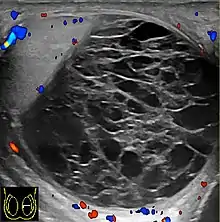

يمكن أن تحدث القيلة الدموية بعد الإصابة (مثل الإصابات الفرشخية) أو يمكن أن يكون من مضاعفات الجراحة. وغالبًا ما يكون مصحوبًا بألم في الخصية. وقد ظهرت الاعراض في المرضى الذين يعانون من الهيموفيليا وبعد إجراء قسطرة الشريان الفخذي. إذا لم يكن التشخيص واضحًا من الناحية الإكلينيكية، فسوف يُظهر التضوء (وضع ضوء مقابل كيس الصفن) سائلًا غير شفاف داخل كيس الصفن. قد يكون التصوير بالموجات فوق الصوتية مفيدًا أيضًا في تأكيد التشخيص. في الحالات الشديدة أو غير المستجيبة للعلاج، قد تكون هنالك حاجة إلى شق جراحي وتصريف. لمنع تكرار الإصابة بعد التصريف الجراحي، يمكن ترك التصريف.